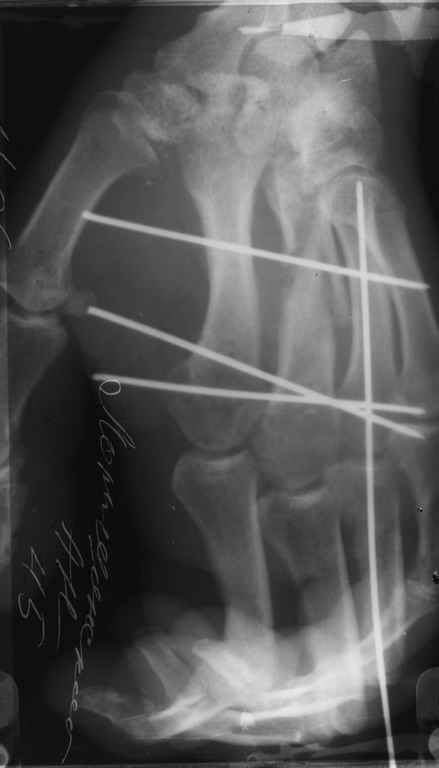

Диагноз на 15.07.05: Стойкая смешанная дермотеногенная контрактура 3,4 пальца правой кисти 3 степени.

-- удалить спицы;

-- сделать рентгенограмму;

Диагноз: Стойкая Смешанная дермотеногенная контрактура 3,4 пальца правой кисти.

Судя по выписному эпикризу, рентгенограммам и фотографиям, пациенту

показано этапное лечение.

К сожалению, мне непонятна локализация кадра

(прилагаю).

Это 3 или 4 межпальцевой промежуток? Гранулирующая рана или свищ?

Зачем спица в 4 Пястной кости?